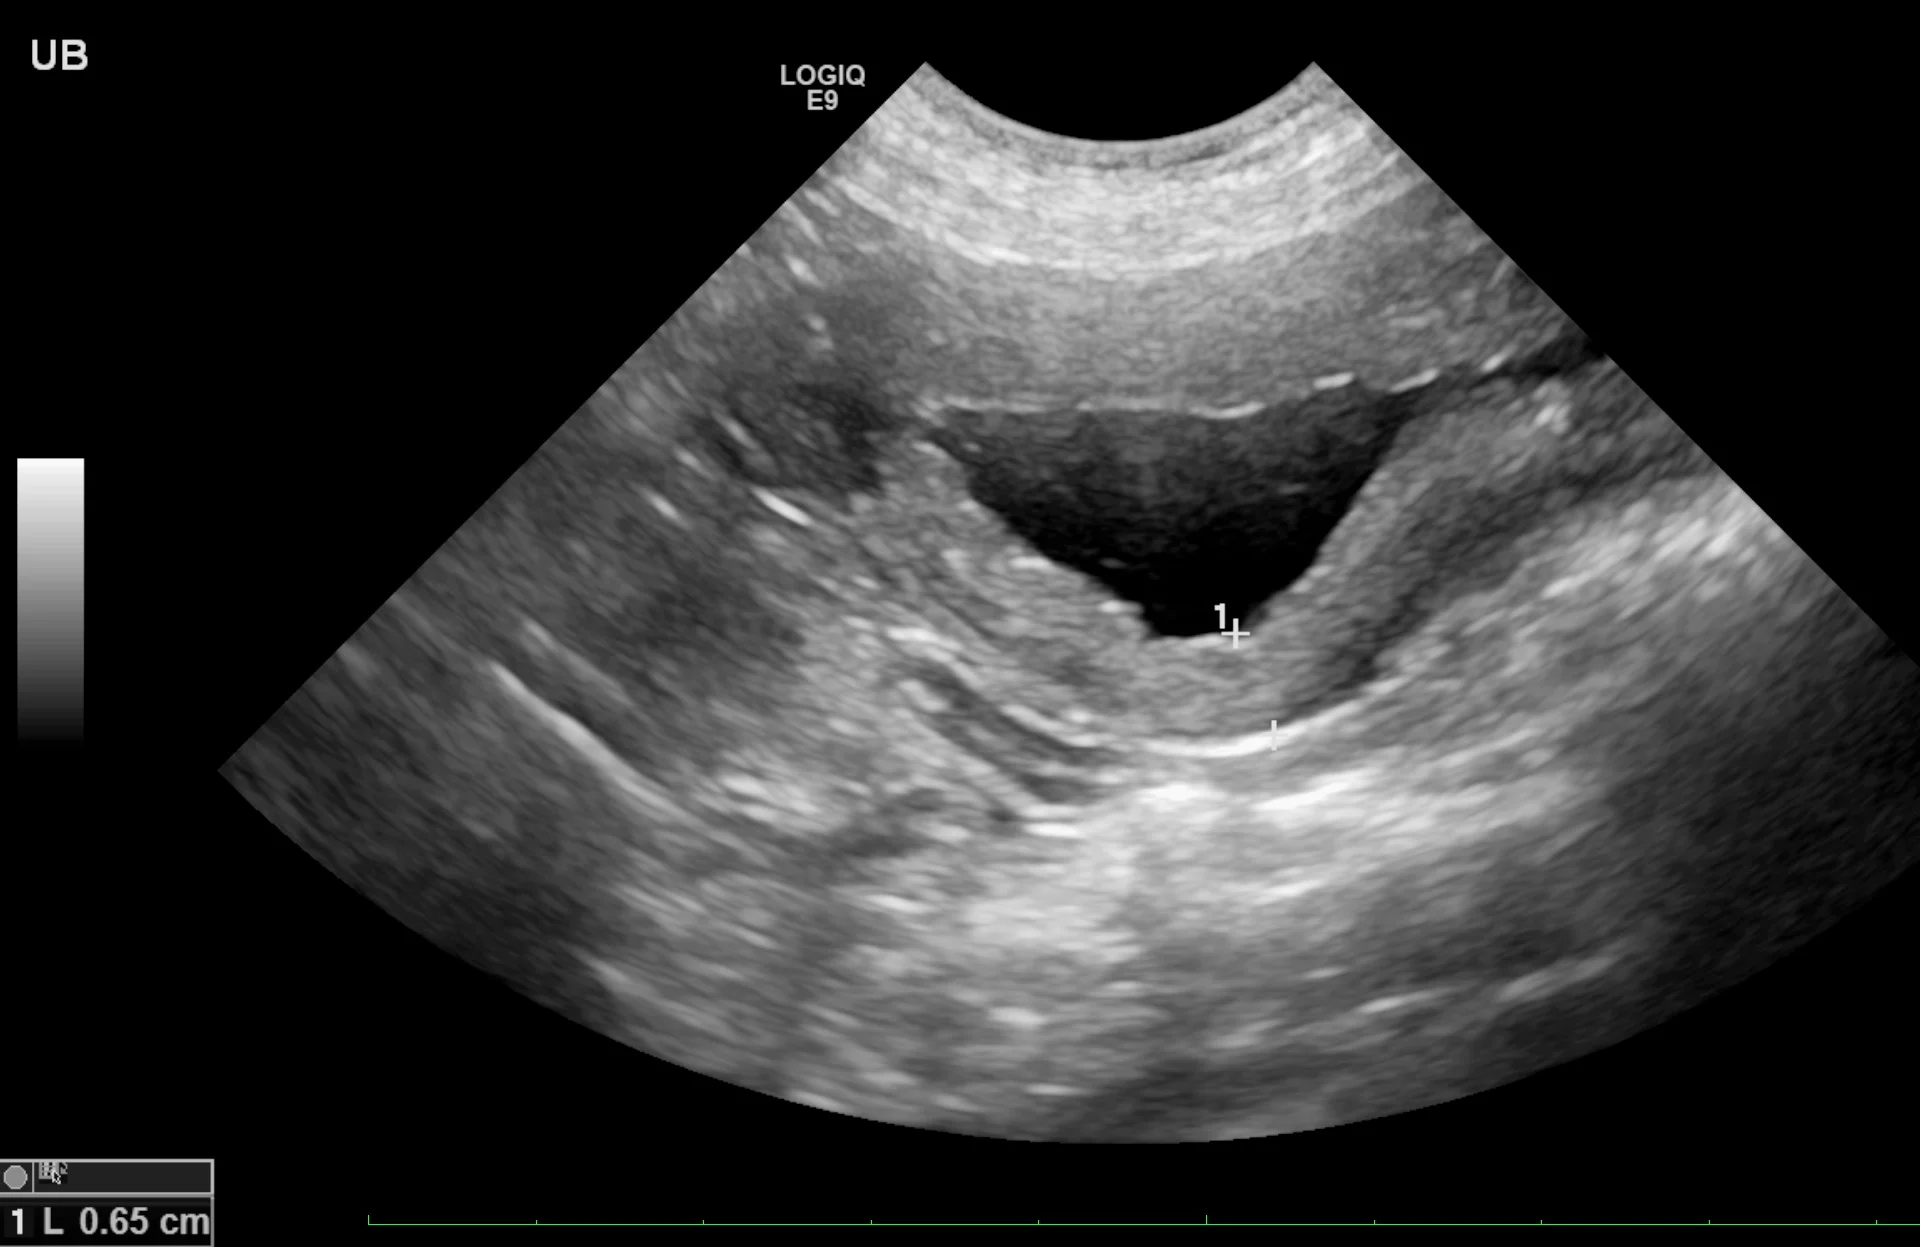

Cystitis is generally a diagnosis of exclusion, especially in cats with hematuria or difficulty urinating (ie, stranguria). Sterile and bacterial cystitis cannot be differentiated on ultrasound, and cystocentesis is needed to further characterize sediment even if hyperechoic foci are identified. The urinary bladder wall may be mildly thick or irregular on the luminal side (Figure 1). When measuring the wall of the urinary bladder, a representative region should be selected and the measurement made from the bladder mucosa to the serosa layer. Care should be taken to remain perpendicular to the wall, not to the ultrasound probe, to minimize measurement enlargement that can occur with obliquity. Overall measurement is more important for repeat evaluation to determine whether the urinary bladder is increasing or decreasing in size; retaining a consistent amount of urine (or catheterizing the patient and adding sterile saline) can help ensure consistent measurements.

Sagittal image of the urinary bladder with a diffusely thick wall due to cystitis. Left, cranial; bottom, dorsal